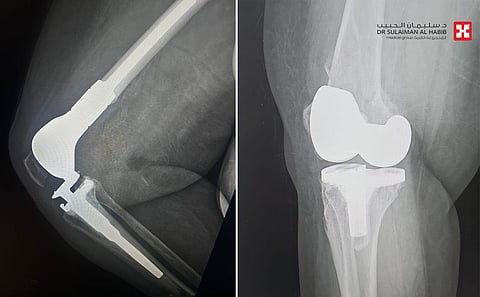

الذي قال أن السيدة حضرت إلى المستشفى وهي تشتكي من آلام حادة وتورم بالطرف السفلي الأيمن، مع عدم القدرة على الحركة والتحمل، إضافة إلى أمراض مزمنة كالشريان التاجي وداء السكري وارتفاع ضغط الدم، وخضعت لفحوصات دقيقة، حيث أظهرت صور الأشعة الطبية كسراً في نهاية عظم الفخذ حول المفصل الصناعي، وتبين عدم قابلية الكسر للتثبيت بالصفائح أو البراغي، بالنظر إلى هشاشة عظام المراجعة وتقدم عمرها، فتم تبني خطة علاجية تناسب الحالة، وأجريت لها عملية جراحية تم فيها استبدال الجزء السفلي من عظمة الفخذ، في تدخل جراحي استمر لـ"4" ساعات، وتكللت ولله الحمد بالنجاح التام، ونقلت المراجعة إلى جناح التنويم.

وأضاف د. شبو الحاصل على الزمالة الفرنسية أن المراجعة بقيت منومة في المستشفى لمدة "7" أيام تحسنت خلالها مع العناية الطبية الحثيثة، ومن ثم غادرت المستشفى بصحة جيدة، ولاحقاً استعادت قدرتها على الحركة وتخلصت من كافة أعراضها، وعادت تمارس حياتها بصورة طبيعية.